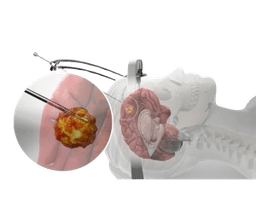

Embolization of Brain & Spinal Tumors

Embolization of the brain and spinal tumor is a technique that blocks the blood vessels artificially, that hold or stop the blood flow to the tumor. As a result, this leads to the tumor that stops supply of blood and oxygen and also results in the slow growth of the tumor or sometimes it is destroyed in the same way. Specifically, tumors in the head and neck along with the spine are usually treated by blocking the blood supply of the tumor by using a special liquid. This procedure is carried out by inserting a thin tube called catheters through the groin or arm and guiding them through the way of blood vessels to the tumor. Alternatively, there is one option more and that is to perform the procedure by going straight through the skin to reach the tumor.